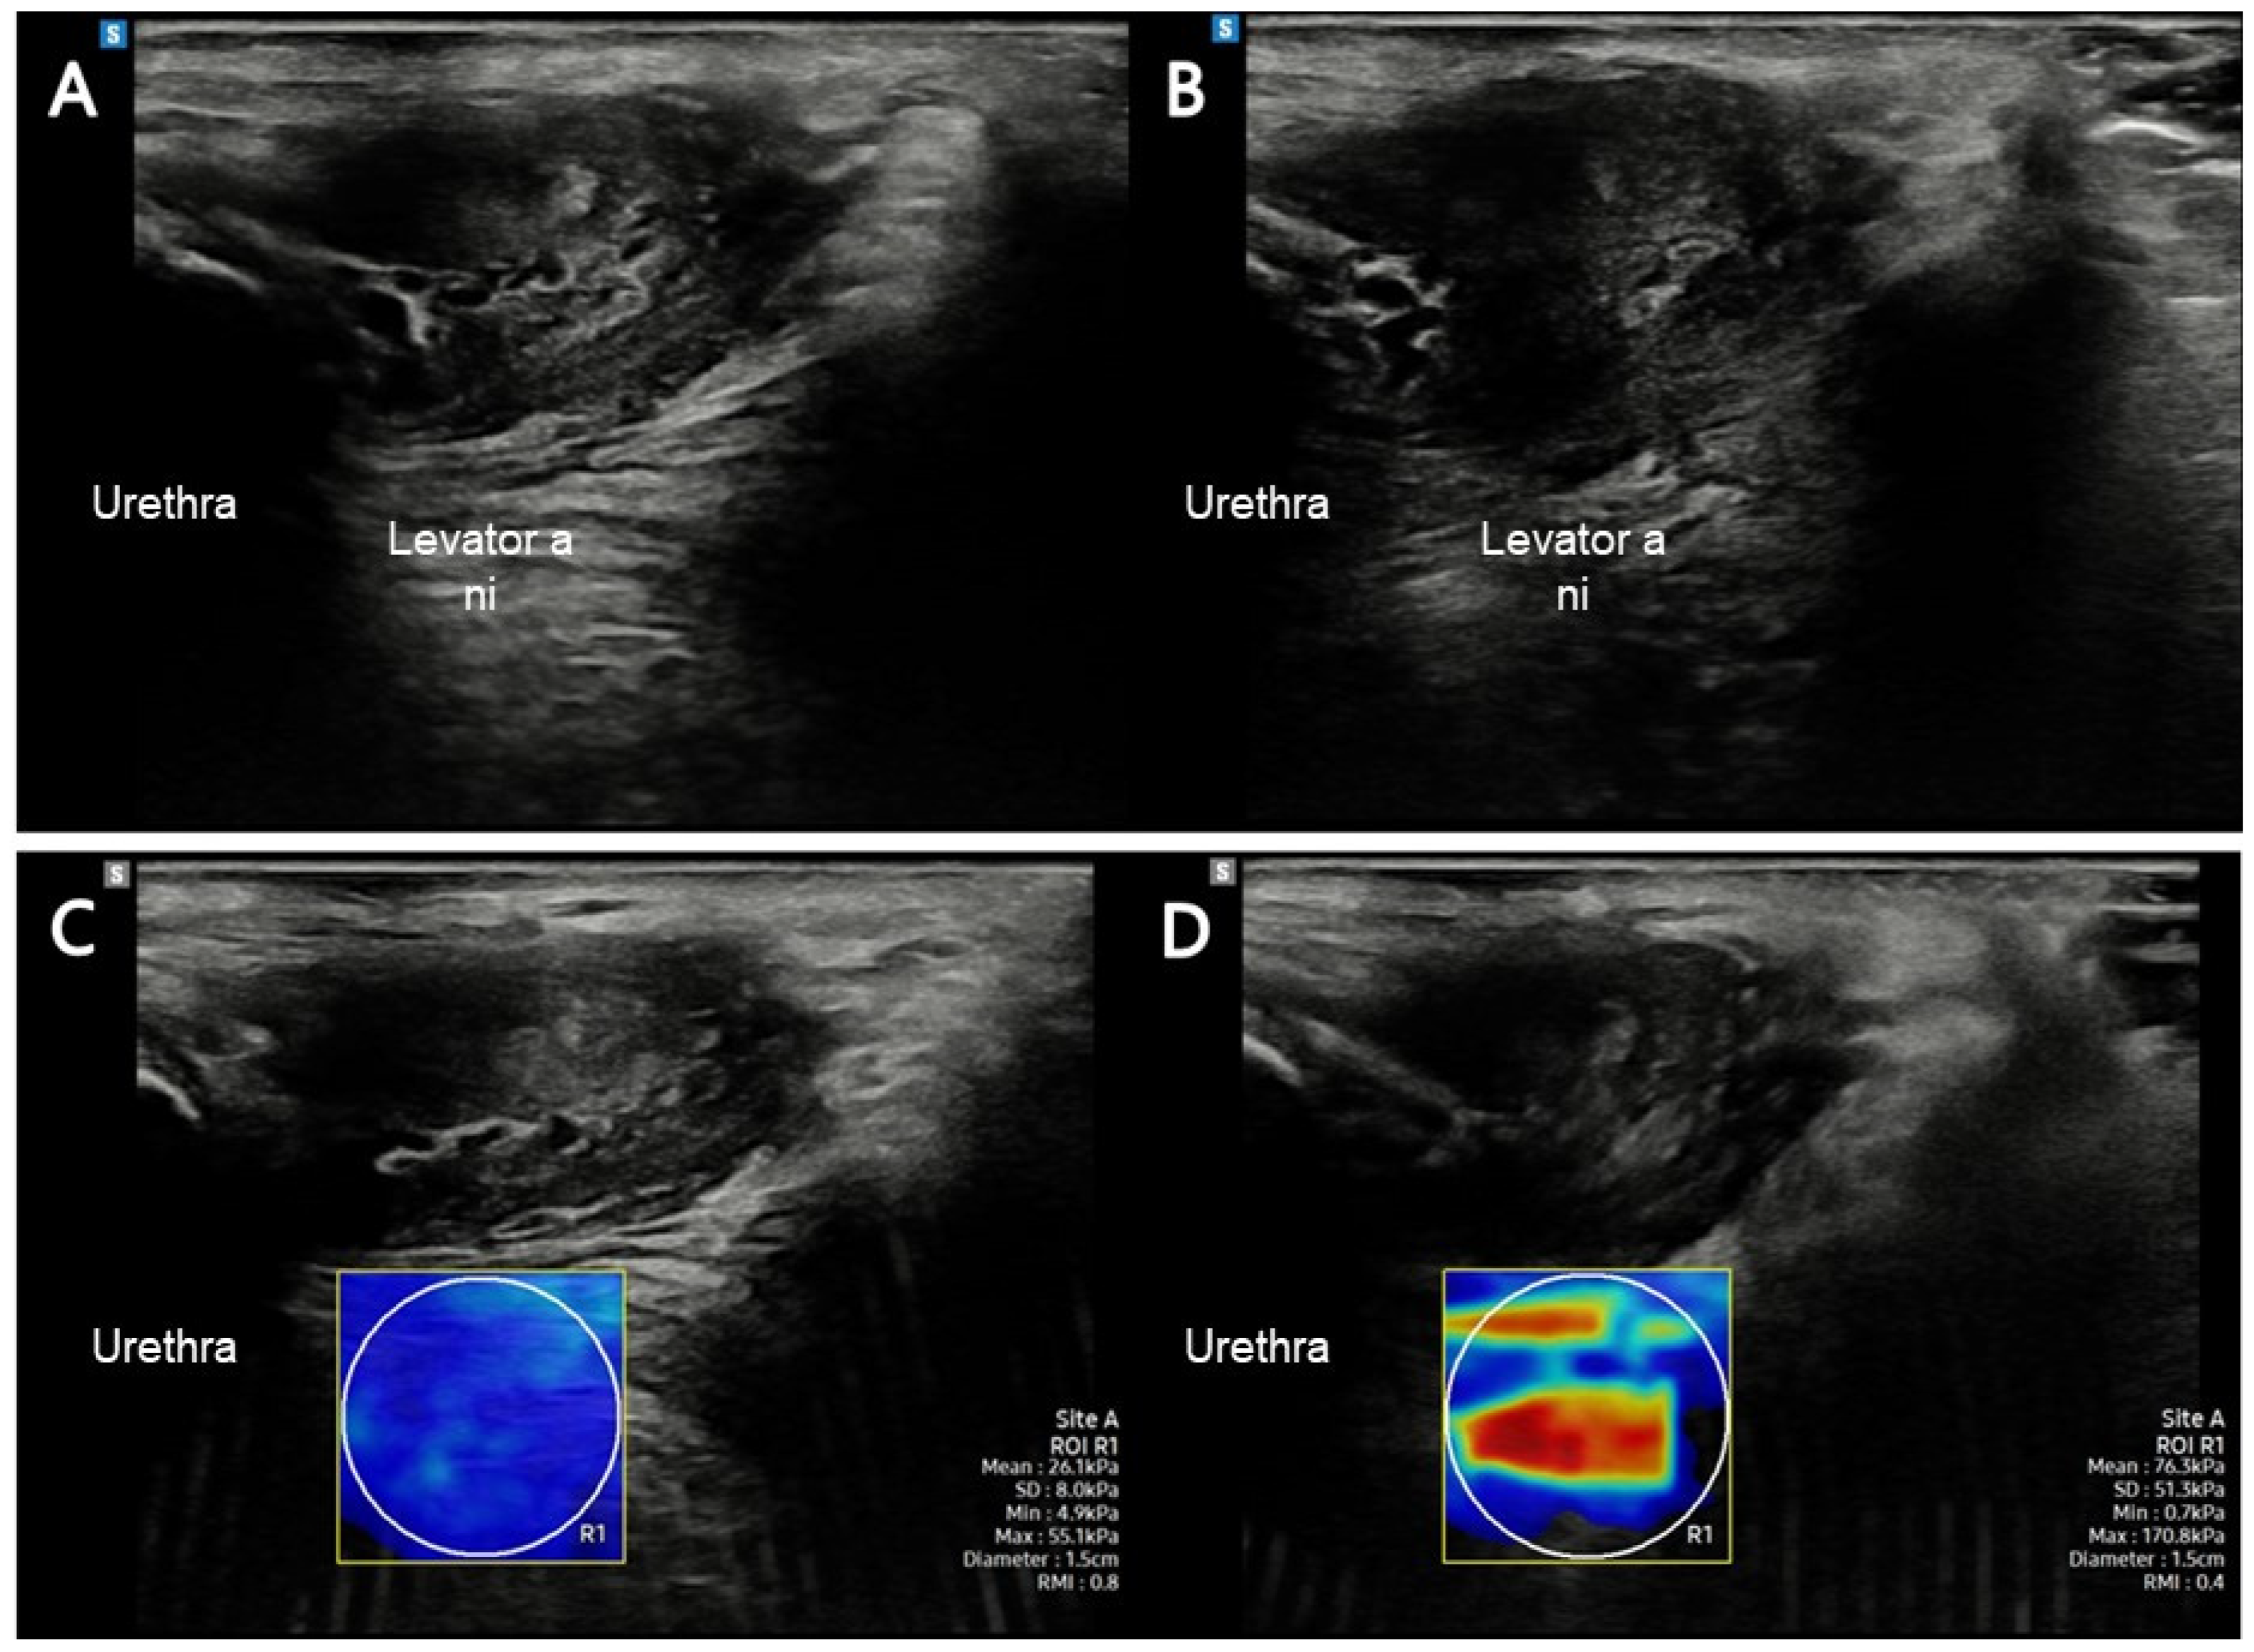

2.5.1. Assessment of PFM (LA) Using SWE

| LA elasticity (kPa) | 24.7 ± 4.5 | 62.1 ± 10.4 * | 34.3–40.4 |